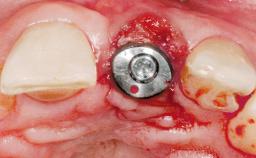

Immediate Flapless Placement of an Implant in a Maxillary Left Central Incisor Site

A 42-year-old female patient was referred to our clinic at the School of Dentistry of the University of São Paulo in November 2004, presenting a deficient restoration in the upper left central incisor. The clinical examination revealed no gingival retraction or any signs of gingival inflammation and, therefore, previous periodontal treatment was not considered. The patient presented a high lip line at full smile and a thin tissue biotype. This combination characterized a high-risk situation from an anatomic point of view, which required careful preoperative planning and cautious surgical execution.

Type of Implants One-Piece

Placement Protocol Immediate implant placement

Tooth Site Maxillary incisor or canine

Socket Morphology Single-root socket

Socket Integrity Sufficient, with intact bone walls

Bone Volume Sufficient, with intact walls